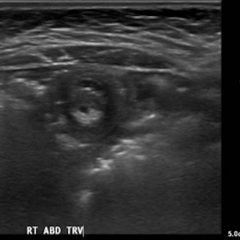

The initial CT scans showed extraluminal gas surrounding the distal esophagus as it traversed the posterior mediastinum, concerning for possible distal esophageal perforation that prompted surgery and GI consultations. There was no evidence of a drainable collection or significant fat stranding. The image also showed an intraluminal stent traversing the gastric antrum and gastric pylorus with no indication of obstruction. Circumferential mural thickening of the gastric antrum and body were consistent with the patient’s history of gastric adenocarcinoma. The shotty perigastric lymph nodes with associated fat stranding, along the greater curvature of the distal gastric body suggested local regional nodal metastases and possible peritoneal carcinomatosis.